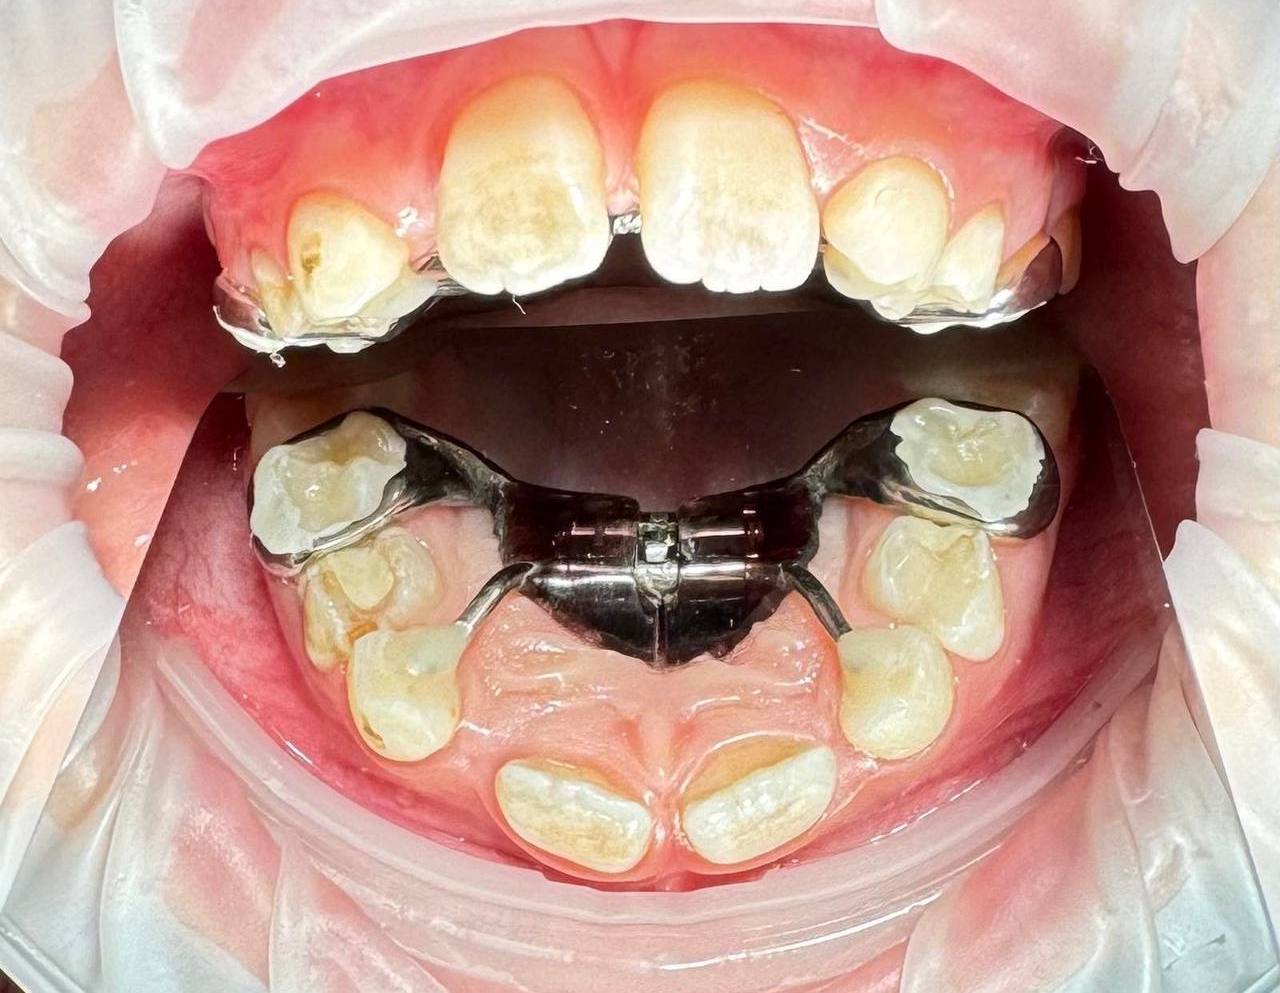

Главная задача аппарата — расширение верхней челюсти. Оно происходит посредством активации винта в центре конструкции. Поворот винта раздвигает пластмассовый базис, который в свою очередь оказывает давление на зубной ряд.

💪🦷Аппарат наиболее эффективен в раннем сменном прикусе – от 6 до 9 лет, и назначается в клинических ситуациях, для решения которых необходимо расширение и нормализация формы верхнего зубного ряда: